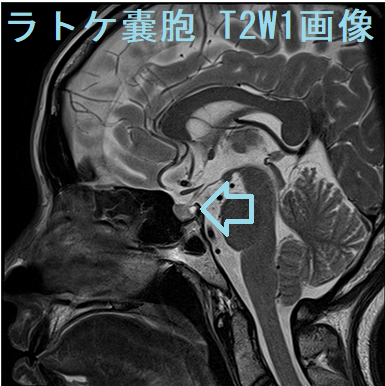

MRI検査では

- T1強調;50% 高信号(蛋白成分が多い)、50% 低信号

- T2強調;70% 高信号、30% 等-低信号

- T1+ Gd造影剤;造影効果なし、周囲辺縁のみ造影される